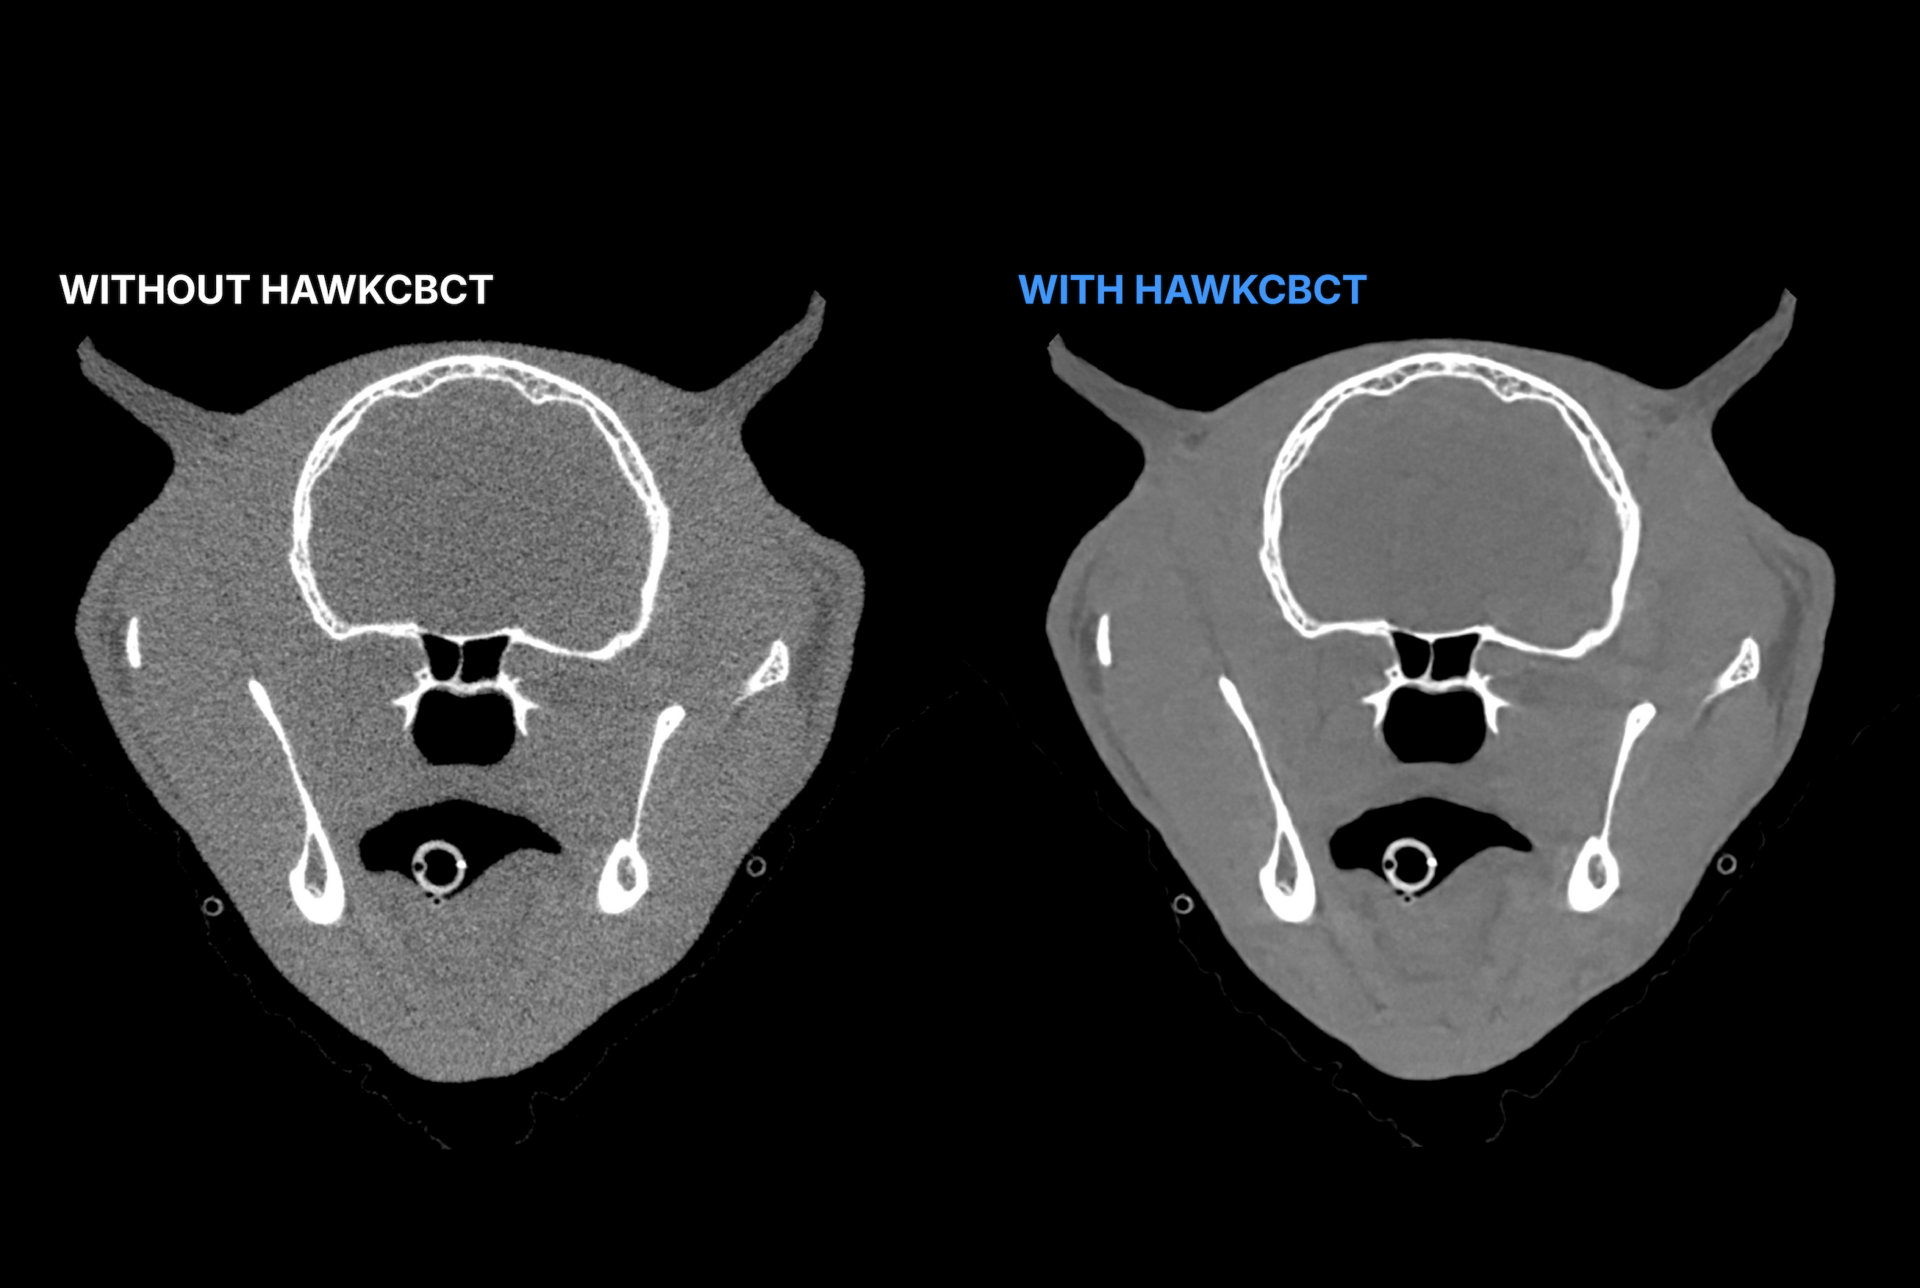

By removing noise and closing the gap with CT image quality, it delivers sharper scans and a higher standard of image consistency. Its advanced enhancement strengthens soft-tissue visualization, giving veterinary teams sharper visibility where it matters most. Integrated seamlessly into existing workflows, HawkCBCT helps clinics save time, streamline image review, and extract more value from every scan. Built exclusively for veterinarians and trained on animal data, it turns CBCT into a more powerful, more reliable imaging asset.